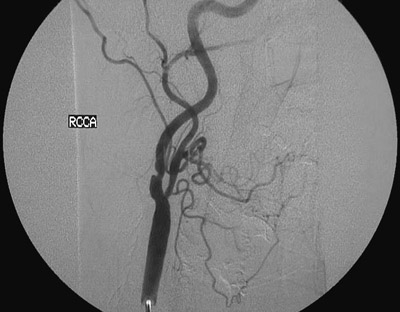

This angiogram demonstrates narrowing of the right common carotid artery in a patient with severe atherosclerosis and a history of transient ischemic attacks.